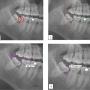

Caries and impacted MTM impaction: (1) Distal caries on MSM; (2) The depth and space of MTM was determined by the Pell & Gregory classification method; (3) The Shiller classification applied in determining the angulation of impacted third molar; (4) The distance between the distal CEJ of the MSM and mesial CEJ of the MTM was calculated as described in Leone classification